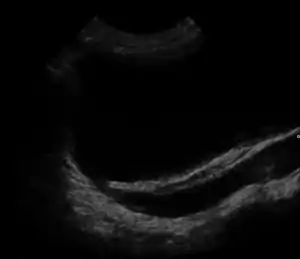

![]() | |

| Ultrasound image showing abnormal vesicoureteral junction and dilated distal ureter resulting in primary vesicoureteral reflux. | |